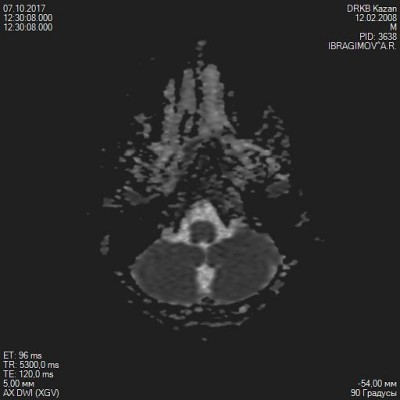

Добрый день, у моего сына 9 лет (12.02.2008г.) в 2016г. начались головные боли с периодичностью раз в 2 мес., пока не вырвет легче не становилось. Прошли много исследований (во вложении приложу), ничего не нашли, невролог прописывала кавинтон, энцефабол, дикарб, аспаркам. В начале октября по квоте попали в ДРКБ г. Казани диагноз бронхиальная астма, там прошла еще невролога, так как участились головные боли в основном преобладают в височной части и лобной, давление поднимается от 112 до 128 (в нормальном состоянии мерили в течении 1 мес. 98-107), температура еле доходит до 36.С ежедневно звонят из школы просят забрать ребенка, чем снимать этот приступ не знаем, она направила еще раз на МРТ прошли еще в Казани (снимки во вложении), врач посоветовал обратиться к нейрохирургу, и коррегировать лечение, но у нас в городе и близ лежащих городах его нет. Заключение МРТ: МР-данные ретроцебеллярной кисты, образования медиальной коры в области валикамозолистого тела кистозного характера, нельзя исключить фактоматосз, глиому. Cпасибо за ранее за ответ надеюсь на вашу помощь.